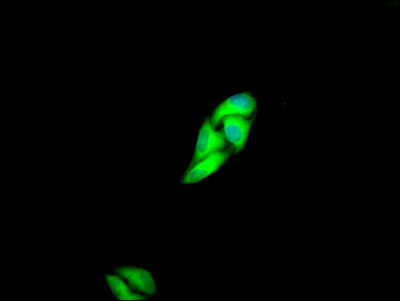

• Immunofluorescence staining of Hela Cells with CSB-RA983271A0HU at 1:50, counter-stained with DAPI. The cells were fixed in 4% formaldehyde and blocked in 10% normal Goat Serum. The cells were then incubated with the antibody overnight at 4℃. Nuclear DNA was labeled in blue with DAPI. The secondary antibody was FITC-conjugated AffiniPure Goat Anti-Rabbit IgG (H+L).